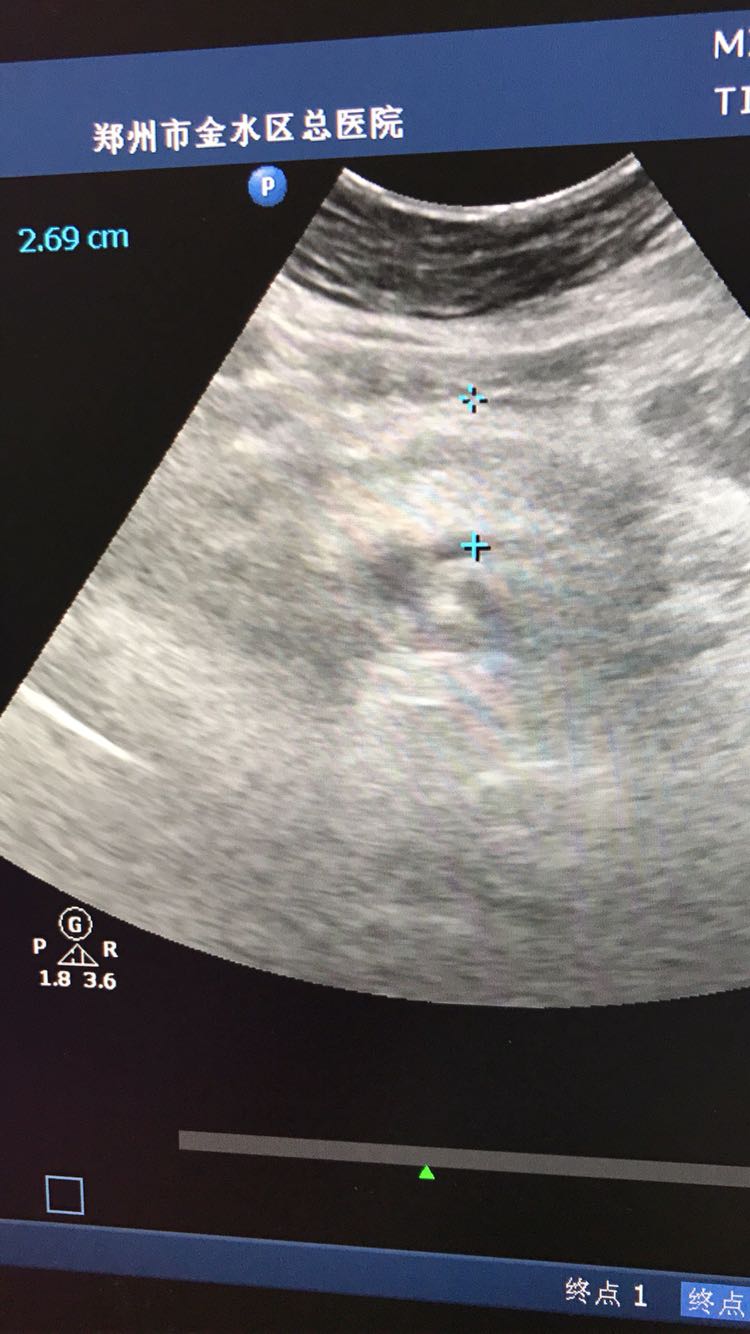

胰腺体积大

患者体检发现

查体 辅查

建议结合临床及其他相关实验室检查